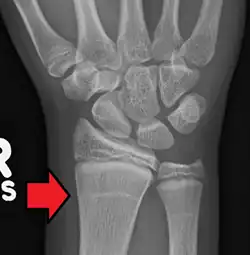

Growth arrest lines in a child with an underlying bone disease | |

Growth arrest lines, also known as Harris lines, are lines of increased bone density that represent the position of the growth plate at the time of insult to the organism and formed on long bones due to growth arrest. They are only visible by radiograph or in cross-section. The age at which the lines were formed can be estimated from a radiograph. Harris lines are often discussed as a result of juvenile malnutrition, disease or trauma. Other studies suggest a reconsideration of Harris lines as more of a result of normal growth and growth spurts, rather than a pure outcome of nutritional or pathologic stress.[1] The lines are named after Henry Albert Harris (1886–1968), professor of anatomy at the University of Cambridge.[2]